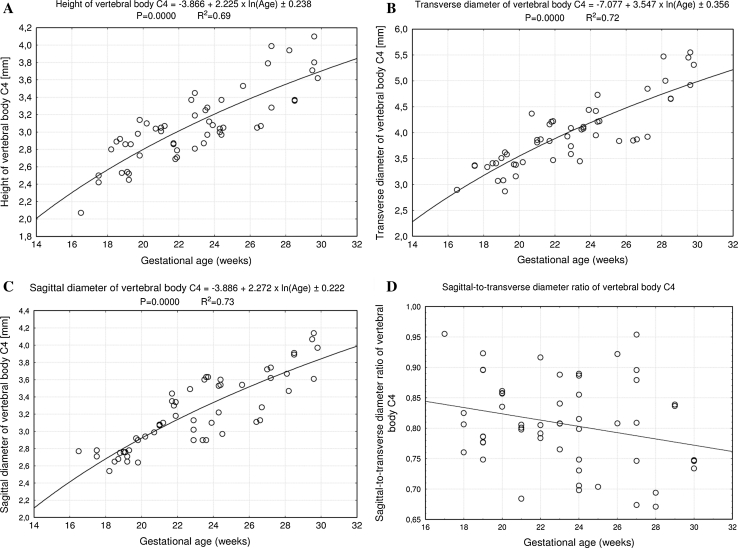

Fig. 2.

Regression lines for height (a), transverse diameter (b), sagittal diameter (c), and sagittal-to-transverse diameter ratio (d) of the vertebral body C4

The size of the C4 vertebral body has been shown in Table 2. The values of the vertebral body height rose from 2.07 to 3.81 ± 0.21 mm for fetuses aged 17 and 30 weeks, respectively. With advancing gestational age, an increase in height (Fig. 2a) followed logarithmically as y = −3.866 + 2.225 × ln(Age) ± 0.238 (R 2 = 0.69). Between ages of 17 and 30 weeks, the transverse diameter of the vertebral body (Fig. 2b) attained the values from 2.90 to 5.31 ± 0.28 mm, in accordance with the logarithmic function: y = −7.077 + 3.547 × ln(Age) ± 0.356 (R 2 = 0.72). During the duration of the study period, the values of sagittal diameter of the vertebral body (Fig. 2c) increased logarithmically from 2.77 to 3.95 ± 0.24 mm, following the formula: y = −3.886 + 2.272 × ln(Age) ± 0.222 (R 2 = 0.73). Consequently, at ages of 17 and 30 weeks, the growth velocities (mm per week) for height and transverse and sagittal diameters of the vertebral body gradually declined with advancing fetal age (P < 0.01), from 0.13 to 0.08 mm, 0.20 to 0.22 mm, and 0.13 to 0.08 mm, respectively. The relative growth of the C4 vertebral body was not proportionate, since the transverse diameter grew much faster than the sagittal diameter. This was expressed by the decrement of the sagittal-to-transverse diameter ratio (Fig. 2d) from 0.84 ± 0.07 to 0.77 ± 0.06 (P < 0.01). The values of cross-sectional area of the vertebral body (Fig. 3a) ranged from 7.50 to 18.33 ± 1.70 mm2 in fetuses aged 17 and 30 weeks respectively, and generated the linear function y = −7.205 + 0.812 × Age ± 1.668 (R 2 = 0.76). During that time the volumetric growth of the vertebral body (Fig. 3b), from 15.53 to 72.43 ± 9.46 mm3, modeled the four-degree polynomial regression y = 14.108 + 0.00007 × Age4 ± 6.289 (R 2 = 0.83).